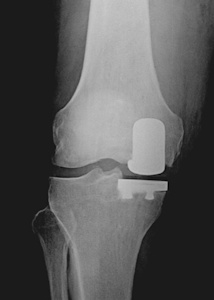

Metal iki yüzey arasında plastik ara-parçadan oluşurlar. Cerrahın tercihine göre bu plastik ara parça hareketli veya sabit olabilir (Resim 2). Dizin iç ve dış yarısı için farklı tasarımları vardır.

Resim 2a,b: Unikondiler protez tipleri